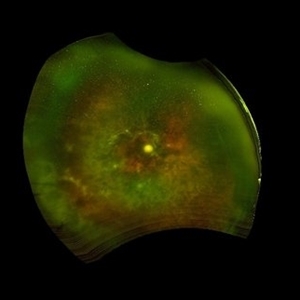

Left eye pseudocolor widefield fundus image of a 57 year old patient with poorly controlled diabetes mellitus, presenting with BE tractional retinal detachment (TRD) on a background of high risk proliferative diabetic retinopathy (PDR). The disc, macula and posterior pole anatomy is obscured and distorted by the extensive tractional fibrovascular component, giving the appearance of a crumpled napkin on this patient's retina.

Photographer: Dr. Shraddha Raj Shrivastava

Imaging device: Nidek Mirante SLO/OCT (Confocal scanning/Spectral domain OCT)